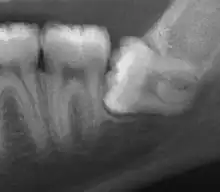

| Impacted wisdom tooth with a horizontal orientation | |